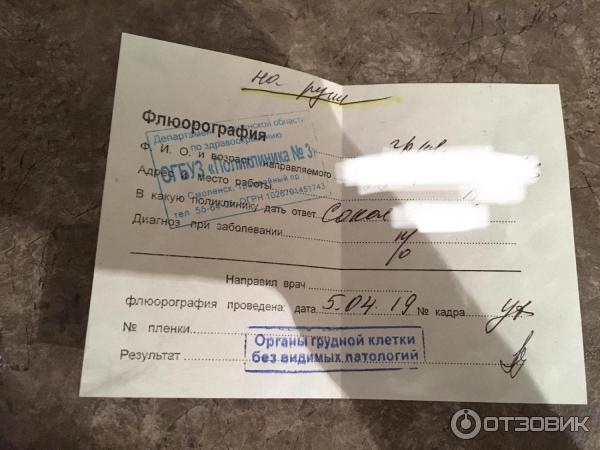

Фотографии рентгеновских снимков без необходимости направления от врача